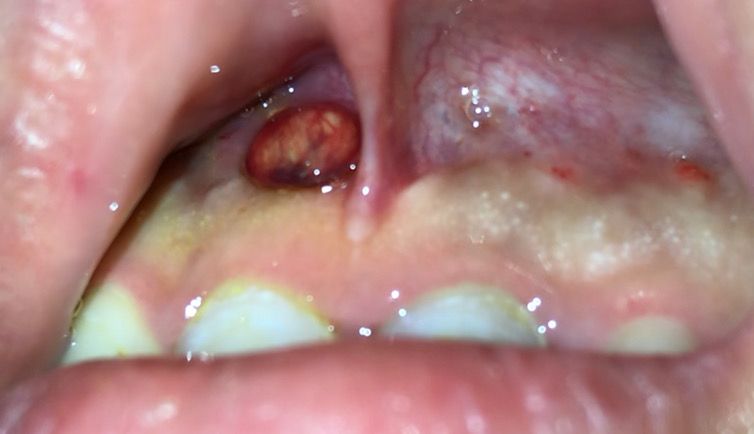

이게 뭔지 알고 싶습니다. 사진 첨부합니다.

치과에서 마취 후 항생제 주사를 맞고 집에 왔습니다. 계속해서 치료 중입니다. 집에 와서 거울을 보니 치아 아래로 노란색 뭔가가 내려와 있길래 면봉으로 걷었습니다. 저게 연고인지 염증 주머니에서 나온 것인지 궁금합니다. 약간 끈적합니다.

사진으로 봤을 경우에는 치아뿌리 끝에 생긴 염증이 바깥쪽으로 나온 것으로 보입니다. 신경관 내부가 감염이 되었을 경우 치조골 내부에 고름이 차게 되고 이것이 누공으로 나오는 경우가 있습니다.

이런 증상은 신경치료가 진행이 되면서 점차 없어지게 됩니다. 자세한 확인을 위해서 치과에서 진료를 받아보는것을 권유드립니다.

면봉에 잇는건 항생제를 넣어 놓은 거 같습니다. 억지로 제거하실필요는 없을것같습니다.

치주농양(고름)이 나온 것으로 보입니다 치과에서 항생제 처방 외에도 배농술 등이 필요한 상황으로 보입니다